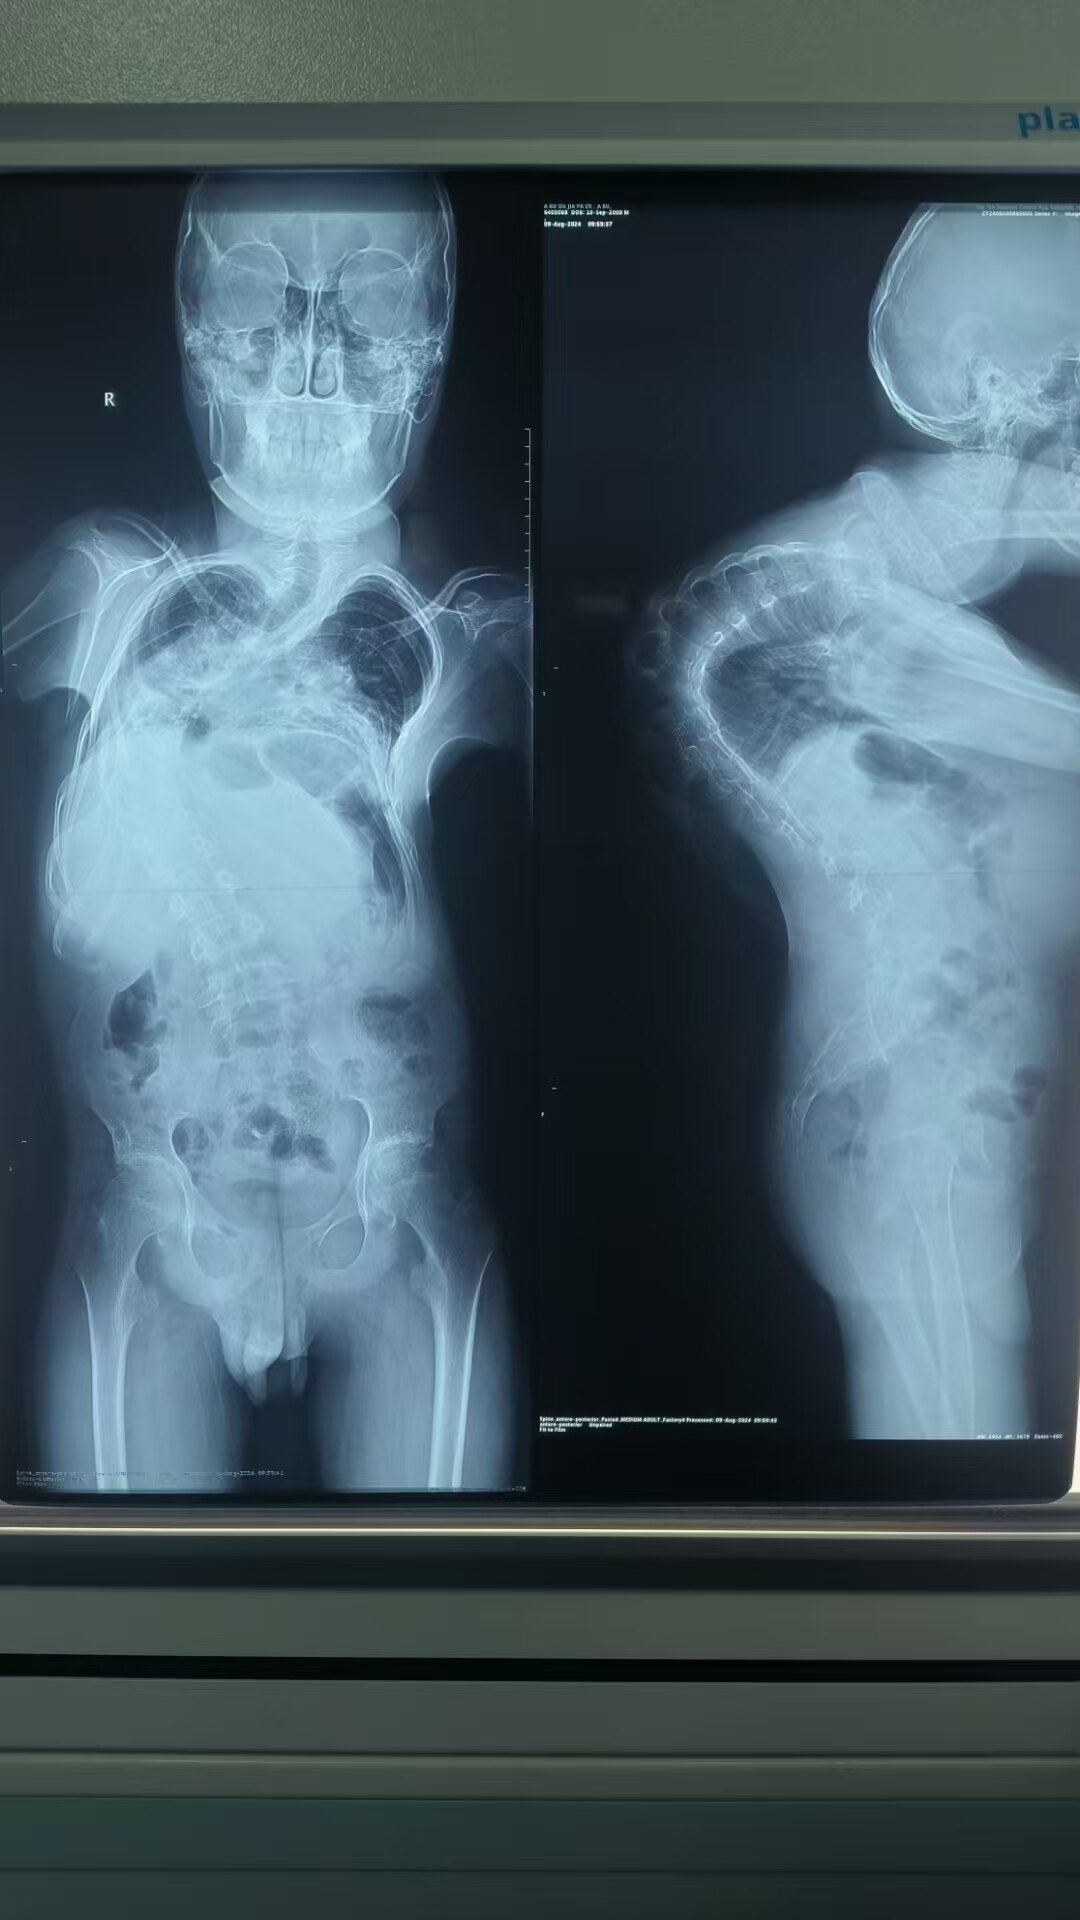

近日,解放軍總醫(yī)院第七醫(yī)學(xué)中心兒科醫(yī)學(xué)部小兒骨科收治了一名來自新疆喀什地區(qū)的重度脊柱側(cè)彎伴后凸畸形的患兒,通過頭盆環(huán)牽引聯(lián)合椎弓根螺釘固定矯形術(shù),讓男孩成功擺脫駝背困擾,長高17厘米。?解放軍總醫(yī)院第七醫(yī)學(xué)中心小兒骨科李文超主任立即組建多學(xué)科專家團(tuán)隊(duì),針對患兒脊柱側(cè)彎畸形角度大、脊柱僵硬及矯治困難的特點(diǎn),為患兒制定了“先矯后術(shù)”的治療方案。采用頭盆環(huán)牽引,通過每天旋轉(zhuǎn)伸縮桿螺母逐漸增加牽引力度,逐漸改善脊柱畸形,并且可以提高心肺功能,增加脊髓神經(jīng)耐受能力,從而降低脊柱矯形手術(shù)的風(fēng)險(xiǎn)及并發(fā)癥。經(jīng)過2個(gè)多月持續(xù)牽引,患兒胸椎段側(cè)彎角度下降至50°,極大增強(qiáng)了家屬的治療信心。由于患兒需要在外架支撐下進(jìn)行手術(shù),頸部無法彎曲,給患兒在手術(shù)體位、麻醉護(hù)理方面都帶來了極大挑戰(zhàn)。整個(gè)手術(shù)麻醉護(hù)理團(tuán)隊(duì)制度了周密的手術(shù)方案,患兒全程在CT導(dǎo)航及神經(jīng)檢測的情況下,完成了13個(gè)節(jié)段進(jìn)行精準(zhǔn)定位及矯正復(fù)位,歷時(shí)8小時(shí)順利結(jié)束,手術(shù)順利結(jié)果。術(shù)后由于患兒椎體形態(tài)的改變,固定器械自身的重量、胸腔與腹腔空間的變化等,術(shù)后對于心肺功能與肢體康復(fù)需要密切觀察與護(hù)理。劉麗護(hù)士長帶領(lǐng)護(hù)理團(tuán)隊(duì)為此制定了精細(xì)的護(hù)理康復(fù)計(jì)劃,護(hù)士細(xì)心的為患兒進(jìn)行循序漸進(jìn)的呼吸功能訓(xùn)練、腰背肌訓(xùn)練、雙下肢功能鍛煉、傷口護(hù)理、體位管理、疼痛護(hù)理、日常生活訓(xùn)練等精細(xì)化照護(hù)。目前小加已經(jīng)下地行走,腰背筆直,之前因體態(tài)異常導(dǎo)致的內(nèi)向孤僻的性格也變得開朗了許多,身高更是增加了寶貴的17厘米。小加說:現(xiàn)在感覺現(xiàn)在呼吸都輕松了!爸爸的臉上也露出了久違的笑容。?科普:頭盆環(huán)牽引治療重度脊柱側(cè)彎。脊柱側(cè)彎是小兒骨科最困難的手術(shù),尤其是重度脊柱側(cè)彎畸形,手術(shù)風(fēng)險(xiǎn)高,治療不當(dāng)容易導(dǎo)致呼吸困難、神經(jīng)損傷、甚至造成截癱。解放軍總醫(yī)院兒科醫(yī)學(xué)部小兒骨科采用頭盆環(huán)牽引聯(lián)合手術(shù)矯正固定,取得了良好的臨床效果。頭盆環(huán)牽引是利用機(jī)械作用,在患兒頭部和骨盆分別進(jìn)行外架固定,通過調(diào)整外架的長度,增加頭部和骨盆間的距離,使脊柱收到持續(xù)的牽引力,可以有效的改變患兒脊柱彎曲程度,從而達(dá)到治療復(fù)雜脊柱側(cè)彎的目的。